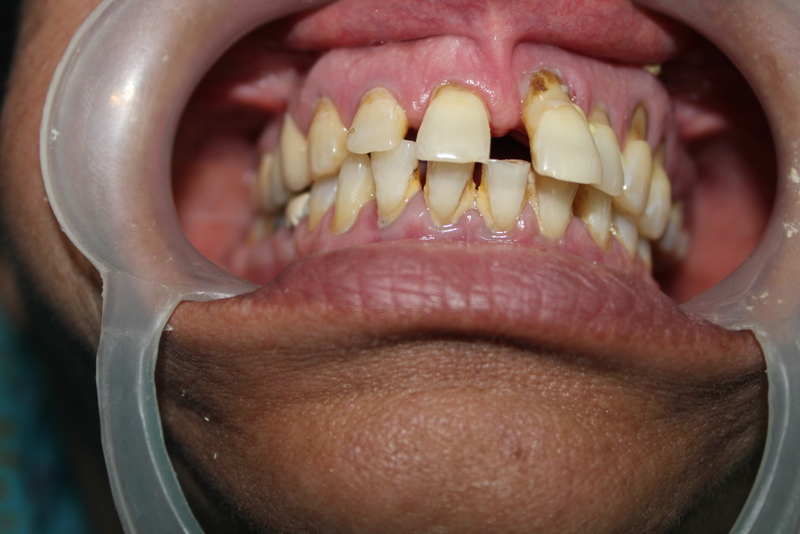

Complete Oral Rehabilitation